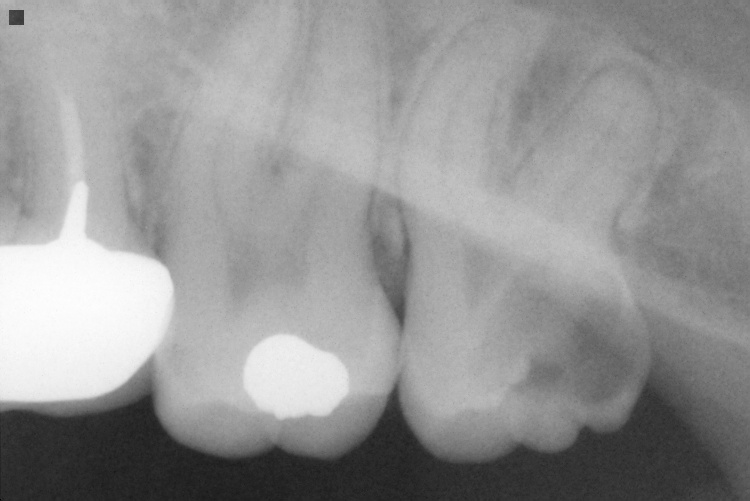

IO000001.jpg

2020-07-28 14:10 80K